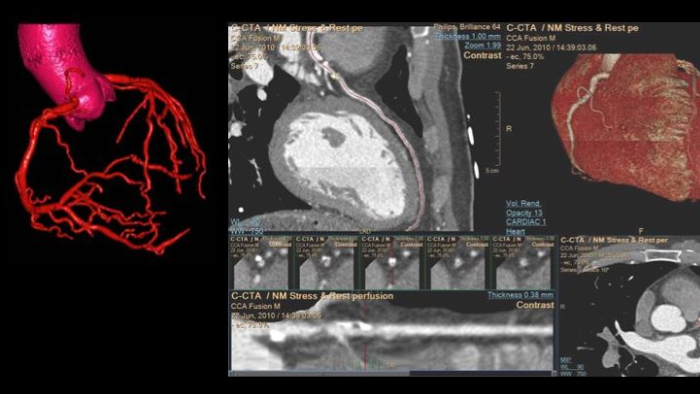

Review, analyze and quantify clinical information from different modalities and for various clinical indications with AI-enabled 3D models, maps and other quantitative tools.

Spectral CT 7500

Unlock the full potential of a Philips CT as a non-invasive cardiac diagnostic tool.